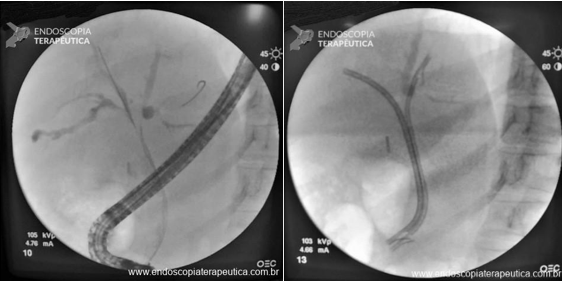

En pacientes con ictericia, la CPRE también puede ser útil para tratar estenosis con la colocación de stents biliares e identificar patrones sospechosos de colangiopatía.

Tratamiento de las estenosis y paliación de la ictericia por CPRE con colocación de prótesis biliares.

Fuente de la imagen: Mendoça EQ. Colangite por IgG4 como diagnóstico diferencial do colangiocarcinoma hilar. Endoscopia Terapeutica 2023, Vol 1. Disponible em: https://endoscopiaterapeutica.net/pt/colangite-por-igg4-como-diagnostico-diferencial-do-colangiocarcinoma-hilar/